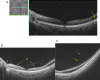

Swept source optical coherence tomography (SS-OCT) was introduced in clinical practice in 2012. Because of its deeper penetration and faster acquisition time, SS-OCT has the ability to visualize choroid, vitreous, and retinal structures behind dense preretinal hemorrhages. Swept source optical coherence tomography has positively influenced and hugely contributed to the research of the vitreous body. It is the first ophthalmic diagnostic technology to demonstrate the entire structure of the posterior precortical vitreous pocket (PPVP) in vivo. The roles of the PPVP in physiological posterior vitreous detachment and vitreoretinal interface disorders have now been elucidated. The presence of a connecting channel between the PPVP and Cloquet's canal suggests that the aqueous humor drains into the premacular space. Deeper penetration of SS-OCT has made it possible to view the choroid. It also has an important role in central serous chorioretinopathy and uveitis. We have also been able to treat Harada disease by monitoring the choroidal thickness by SS-OCT.